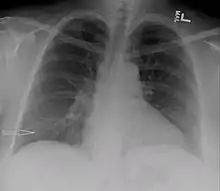

Chest X-ray showing urinothorax disappearing after treatment

Treatment mainly consists of treating the underlying disorder of the genitourinary tract.[2] It requires a multidisciplinary team that includes a pulmonologist and urologist. A nephrostomy tube or Foley catheter can be used to relieve any underlying obstruction. Any injuries are repaired.[11] When the underlying disorder is addressed, the urinothorax rapidly resolves. Thoracic surgery is usually not needed,[4] especially if respiratory symptoms are minimal or nonexistent.[2] Pleurodesis is also ineffective.[11] A chest tube can be used to drain urine from the pleural cavity.[12]